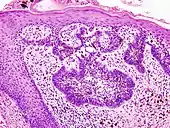

Ductal carcinoma in situ (DCIS) in breast tissue, cell nuclei (blue-purple), extracellular material (pink).

H&E is the combination of two histological stains: hematoxylin and eosin. The hematoxylin stains cell nuclei a purplish blue, and eosin stains the extracellular matrix and cytoplasm pink, with other structures taking on different shades, hues, and combinations of these colors.[5][6] Hence a pathologist can easily differentiate between the nuclear and cytoplasmic parts of a cell, and additionally, the overall patterns of coloration from the stain show the general layout and distribution of cells and provides a general overview of a tissue sample's structure.[7] Thus, pattern recognition, both by expert humans themselves and by software that aids those experts (in digital pathology), provides histologic information.

Hematoxylin principally colors the nuclei of cells blue or dark-purple,[6][15][14] along with a few other tissues, such as keratohyalin granules and calcified material. Eosin stains the cytoplasm and some other structures including extracellular matrix such as collagen[5][7][14] in up to five shades of pink.[8] The eosinophilic (substances that are stained by eosin)[5] structures are generally composed of intracellular or extracellular proteins. The Lewy bodies and Mallory bodies are examples of eosinophilic structures. Most of the cytoplasm is eosinophilic and is rendered pink.[10][15] Red blood cells are stained intensely red.